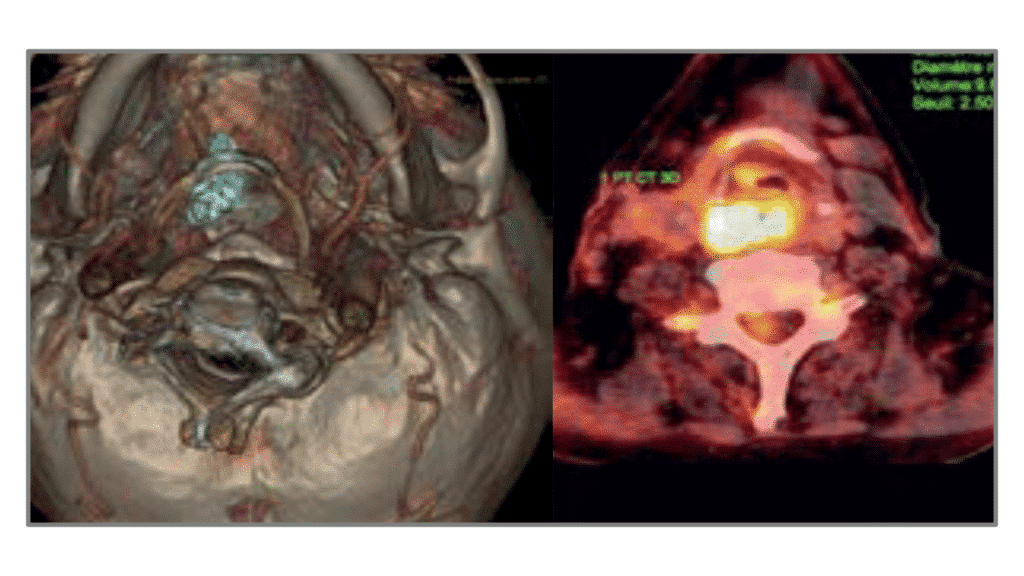

Le DU Carcinologie cervico-faciale offre une formation sur la prise en charge et le traitement des tumeurs et des cancers de la tête et du cou.

Le DU Carcinologie cervico-faciale propose un tour d’horizon des tumeurs et cancers de la tête et du cou ainsi que sur les modes de prise en charge, leur diagnostic et leur traitement.

Le DU Carcinologie cervico-faciale s’articule autour de différents thèmes :

- Notions générales de carcinologie cervico-faciale

- épidémiologie

- histoire naturelle des cancers

- pathologie

- moyens diagnostiques

- facteurs pronostiques

- bases théoriques des traitements

Étude détaillée de toutes les localisations.